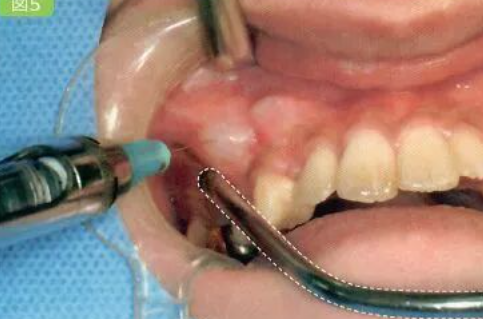

置开口器,发现新鲜血液自咽部涌出,考虑出血来自舌根部可能,清除舌体皮瓣间血凝块,探查发现舌根部一小静脉活动性出血,予确切结扎止血,同时行舌创面缝扎止血观察再无活动性出血后,复位皮瓣缝合。